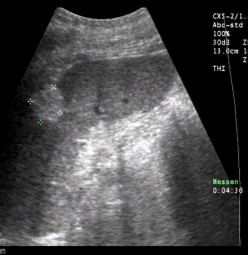

Identify this image.

Splenic abscess